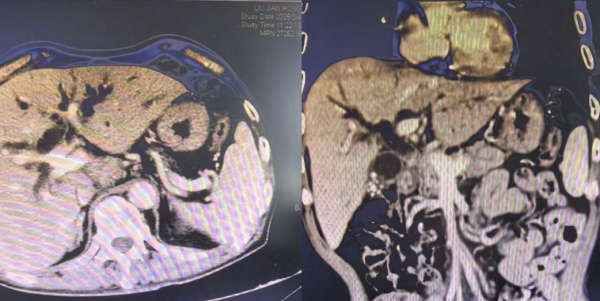

患者胆总管受压,肝内胆管重度扩张

胆道支架植入后胆道梗阻解除

胆总管支架术后改变,肝内胆管无明显扩张